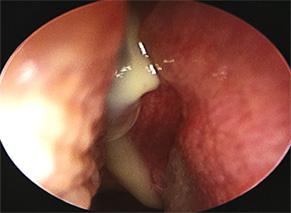

La OMSC se caracteriza por secreción purulenta del oído medio que es crónica (por lo general> 6 semanas) y pérdida de audición asociada con una perforación de la membrana timpánica. La otorrea puede ser recurrente o persistente. La OMSC suele ser indolora. El examen físico en pacientes con OMSC típicamente revela una gran perforación central de la

Figura 21. OMCS, nótese la perforación redonda en la pars tensa, signos inflamatorios y secreción purulenta.

membrana timpánica y drenaje purulento del oído medio. Por lo general, el edema del CAE es mínimo o nulo.

El diagnóstico de OMSC se basa en hallazgos clínicos consistentes (por ejemplo, pérdida auditiva, otorrea crónica). No se requieren cultivos para hacer el diagnóstico inicial y generalmente se reservan para enfermedades que no responden. La condición más común e importante en el diagnóstico diferencial de OMCS es el colesteatoma, que también puede presentarse con hipoacusia y/u otorrea crónica. Puede ser difícil distinguir las dos entidades, ya que el colesteatoma también puede ocurrir junto con la OMCS.